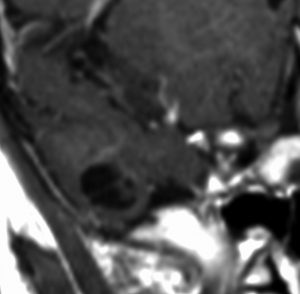

乳児期にてんかん発作で発症する内側側頭葉過誤腫

mesial temporal hamartomatous tumor

乳児期に全身性感帯痙攣発作で発症しました。左海馬鈎に強い石灰化があります。側頭葉硬化症とも言われるものです。この部位の過誤腫様の腫瘍は難治性てんかんとなることが多く,病変切除が必要となります。

脳波では前頭葉に蕀律動を認めます。切除は扁桃体と海馬鈎の摘出を目指すものです。